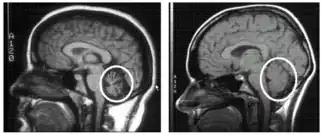

Cerebellum (labeled bottom right) of the human brain. It is located above the brain stem, posterior to the brain. | |